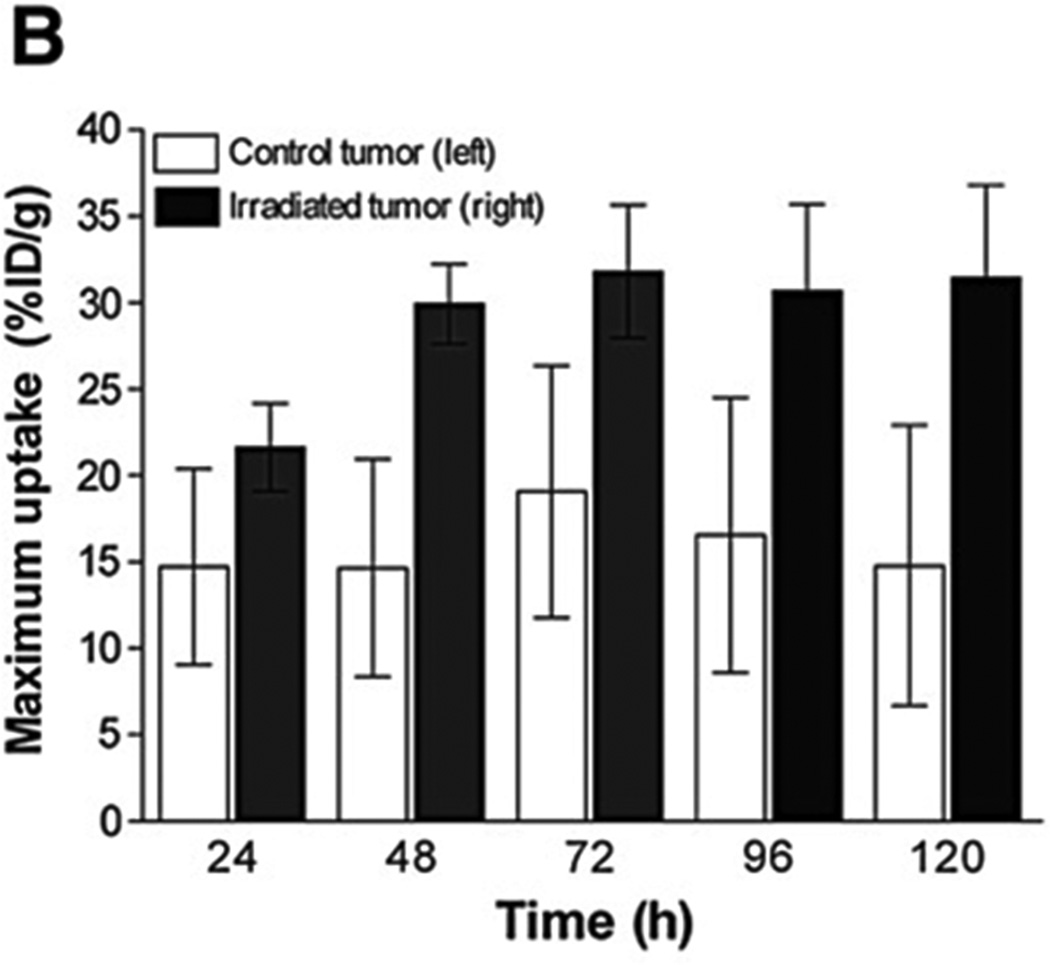

Figure 2.

PSMA+ cells’ responses to different treatments in vitro. (A) The monoclonal antibody 7E11 binds to an intracellular epitope of PSMA, labeling apoptotic or already dead cells, whose leaky cell membrane permits access of the antibody to the intracellular domain. The monoclonal antibody J591, recognizes the extracellular domain of PSMA and thus binds to all PSMA-positive cells, regardless of their viability. (B) Higher percentage of 7AAD and 7E11 stained cells is observed over time with flow cytometry after treatment compared to control (P<0.05). (C) Corresponding staining is observed for both 7E11 and 7AAD staining, a marker of late apoptosis (and thus cell death) after treatment with etoposide (PC3/PSMA+ cells). With permission from Ruggiero A et al. (2012) J Nucl Med 52(8):1608-15